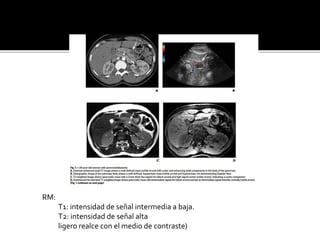

RM:

T1: intensidad de señal intermedia a baja.

T2: intensidad de señal alta

ligero realce con el medio de contraste)